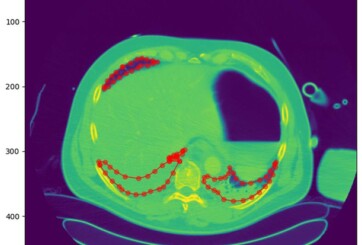

KI ermöglicht sekundenschnelle Diagnose von Lungenverletzungen

Die Segmentierung von Lungen-CT-Bildern ist ein essenzieller Schritt in der Diagnostik schwerer Lungenverletzungen. Das herkömmliche Verfahren kann bis zu drei Stunden beanspruchen. Forschern der Westsächsischen Hochschule Zwickau (WHZ) ist es nun gelungen, das Procedere in Sekunden zuverlässig durchzuführen. Das Forscherteam der Data Science Research Group an der WHZ, angeführt von Prof. Mike Espig, hat in enger Zusammenarbeit mit Prof. Andreas Reske, Chefarzt am Heinrich-Braun-Klinikum Zwickau, einen innovativen Ansatz zur Diagnostik von Lungenverletzungen vorgestellt. Mittels modernster KI-Methoden wurde ein Algorithmus entwickelt,…